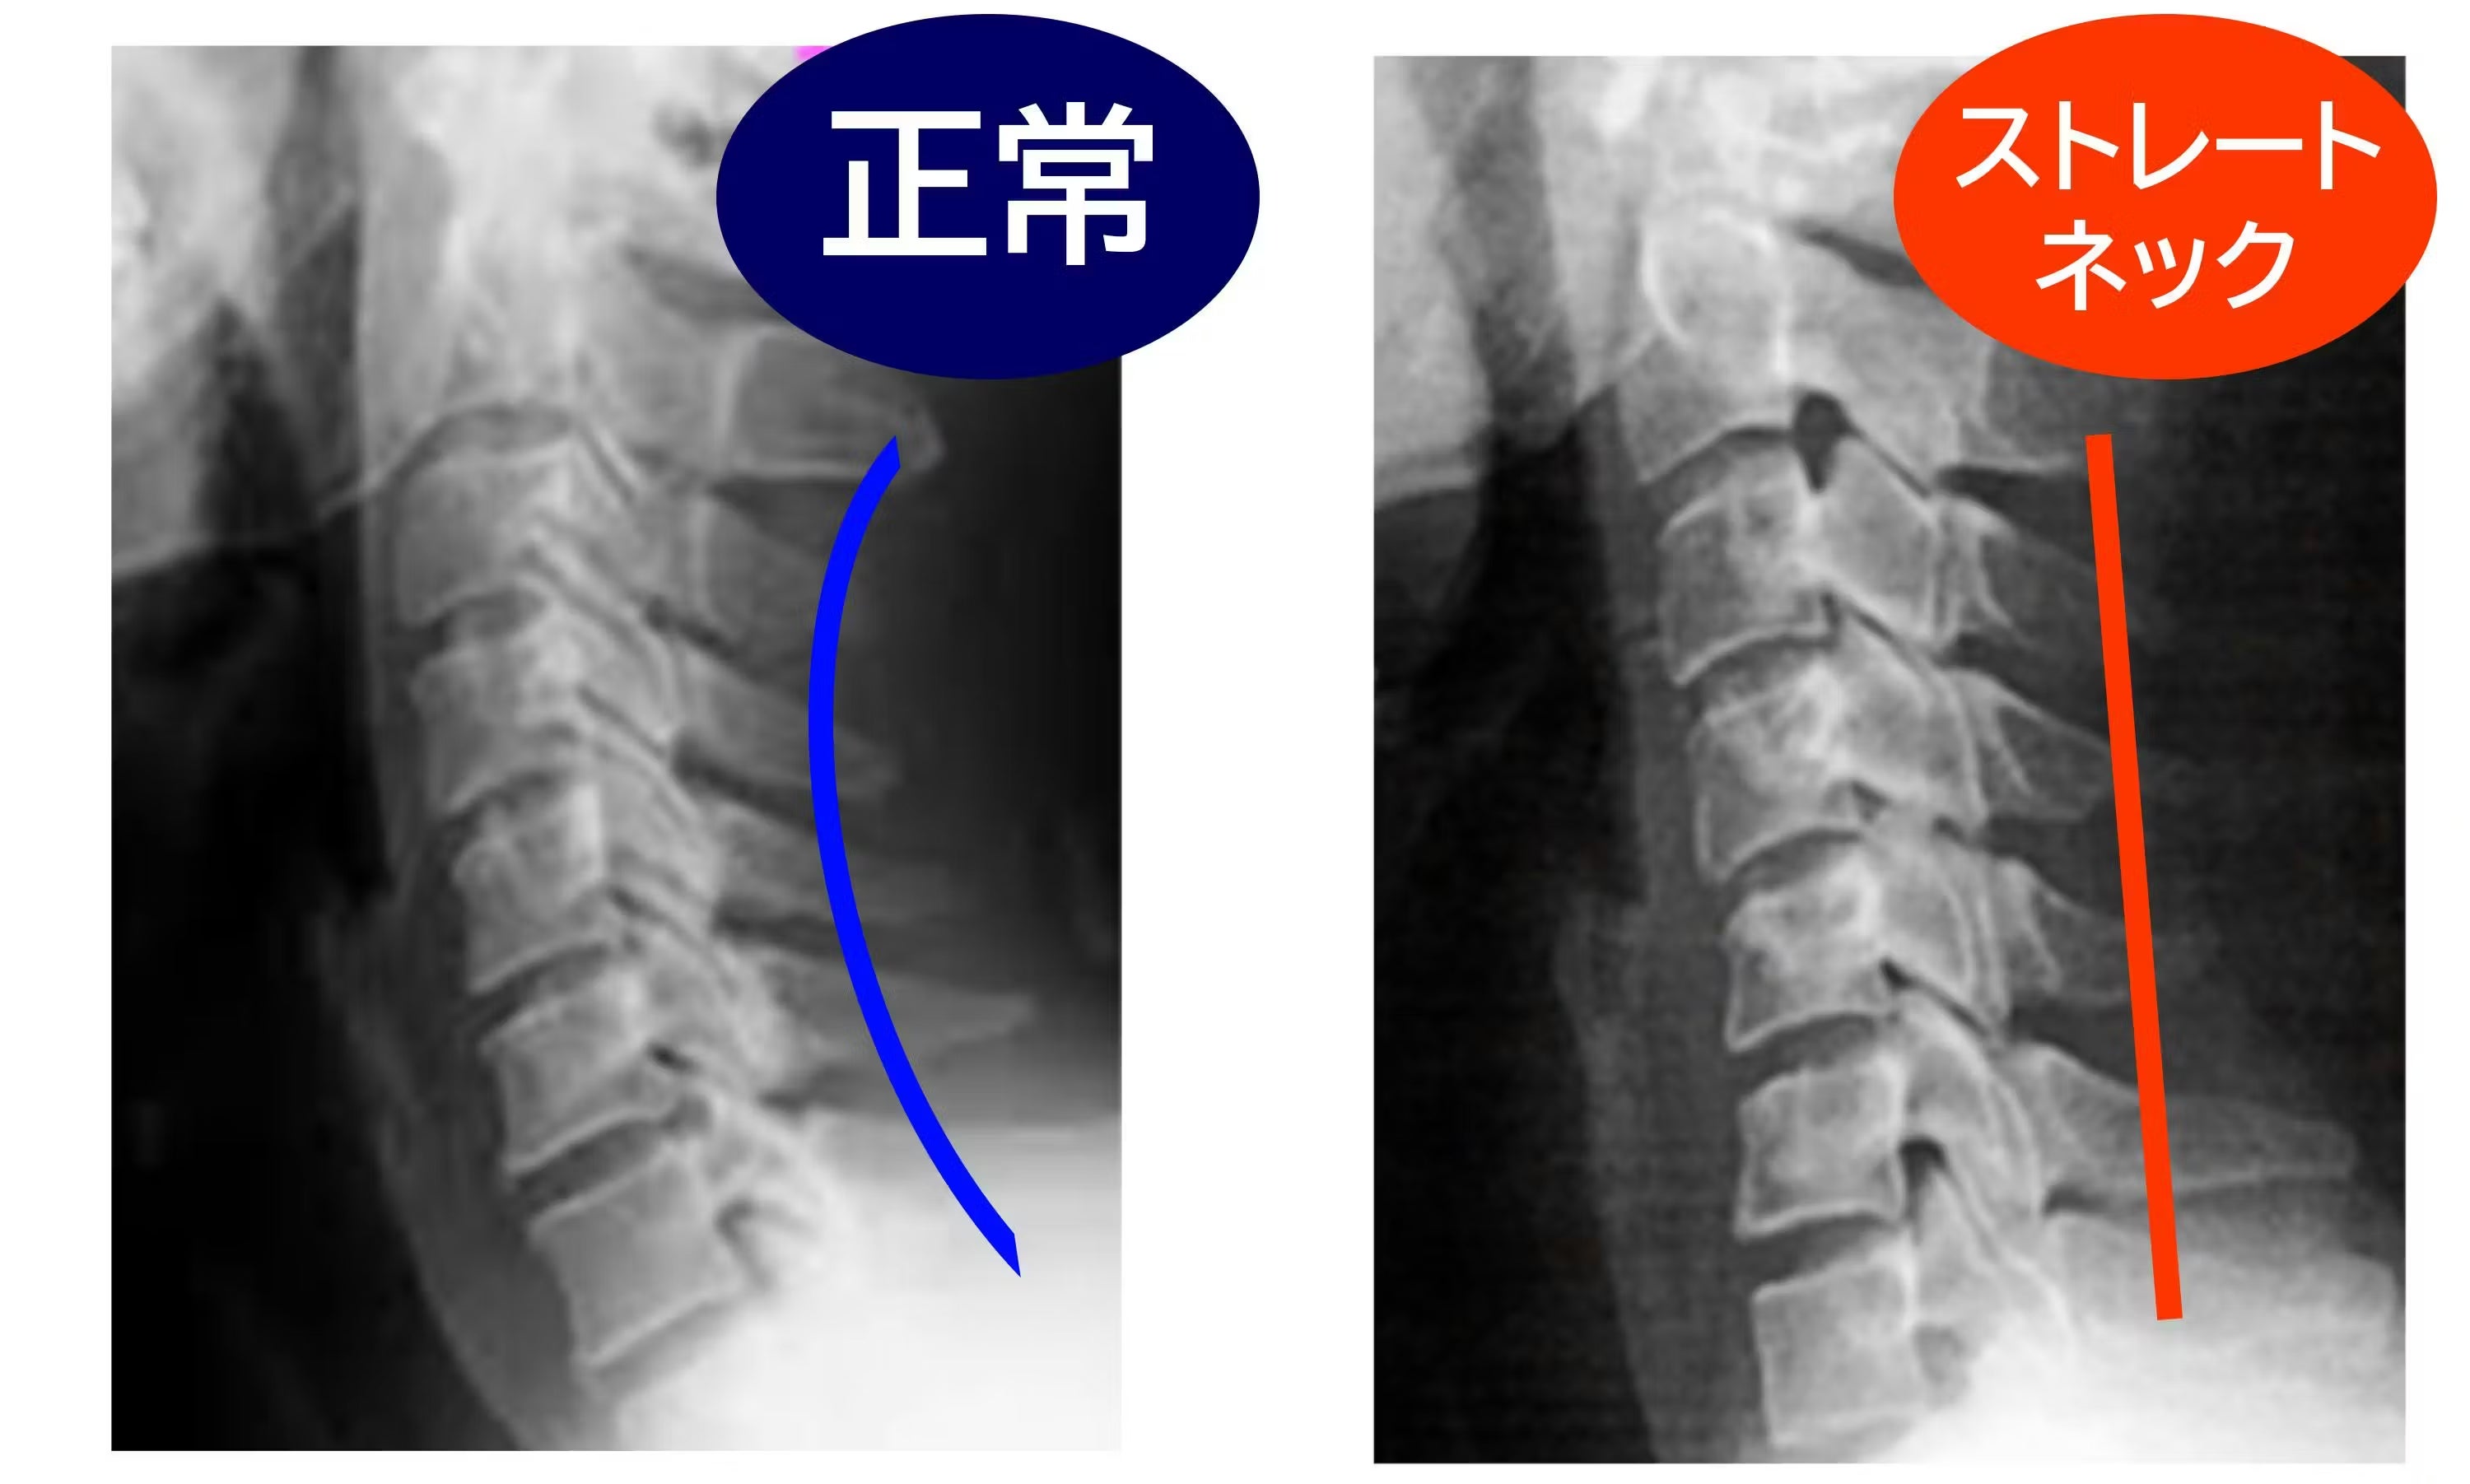

Q:首に異常がある場合でも使えますか?

A:頸椎ヘルニアや重度の首の疾患をお持ちの方、医師の治療を受けている方は、ご使用前に必ず医師にご相談ください。